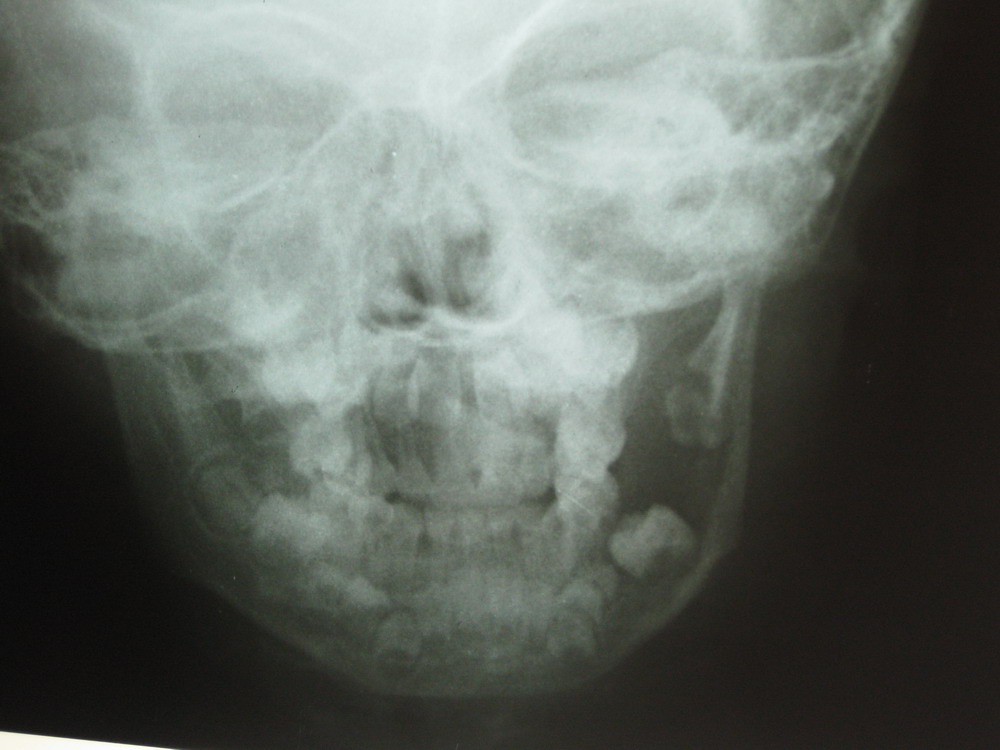

小儿面部肿胀一周

左侧下颌体部溶骨性骨质硬坏,破坏边界欠清,边缘无显著硬化,牙列不齐,牙根亦有骨质溶解,考虑下颌骨牙源性囊肿可能性大,建议ct检查,患者症状急发,考虑合并感染,不知有否其他症状如疼痛,发热等

左下颌骨呈溶骨性破坏,边界尚请。左恒牙牙根部骨质破坏、缺损。结合症状考虑含牙囊肿并感染。建议ct带除外肿瘤样变。

左侧下颌体部溶骨性骨质硬坏,破坏边界欠清,边缘无显著硬化,牙列不齐,牙根亦有骨质溶解,考虑下颌骨糙釉细胞瘤或嗜酸性肉芽肿或牙源性囊肿可能性大

左侧下颌体部及角部溶骨性骨质硬坏,破坏边界欠清,边缘无显著硬化,牙列不齐,相邻牙根亦有骨质溶解吸收,考虑下颌骨糙釉细胞瘤或下颌骨肉瘤,建议结合ct检查。